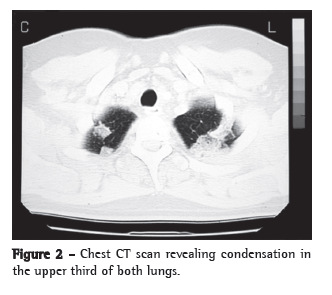

A chest X-ray, performed two months after the onset of symptoms, showed bilateral apical pulmonary opacification and mild left hilar lymph node enlargement (Figure 1). Chest CT scans showed condensation in the upper third of both lungs (Figure 2), as well as left hilar lymph node enlargement and right pleuritis (Figure 3). A sinus X-ray was normal.

In the case reported here, the primary focus was located in the upper thirds and in the apices of the lungs, reaching the pleura, which caused the patient to receive anti-inflammatory medication to control the chest pain. In addition to primary infection, acute lung injury caused by paracoccidioidomycosis has rarely been observed in the regressive,(10) acute or subacute(3,4) forms. Unlike the chronic form of the lung disease, the forms more temporally related to the fungal infection present pulmonary involvement that is heterogeneous in terms of type and location. One review of pediatric juvenile paracoccidioidomycosis included patients with alveolar consolidation, interstitial infiltrate, micronodules, nodules and pleural effusion.(11) There have also been reports of an adult who presented with cortico-pleuritis(1) and a young individual who had empyema and bilateral pulmonary consolidation, P. brasiliensis being detected in the bronchoalveolar lavage fluid.(3) The acute injury caused by paracoccidioidomycosis can be located in the apex, the perihilar region, the juxtapleural region and the base of the lungs, or have a disseminated aspect.(3,11) Conversely, P. brasiliensis was isolated from the respiratory secretion of patients with the acute or subacute form of